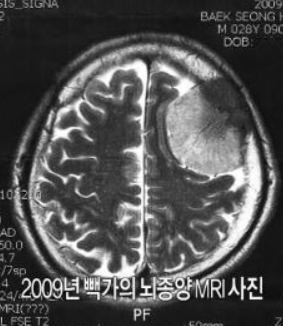

하지만 막 작가로서 자리를 잡기 시작하던 2009년 빽가는 뇌종양 판정을 받으면서 다시 한번 큰 위기를 맞았습니다. 29살 나이에 생명이 위태롭다는 진단을 듣고 절망한 빽가는 2주 동안 집에 갇혀 울기만 했죠. 다행히 2010년 생명을 건 뇌종양 수술을 성공적이었고 투병 이후 빽가는 보다 적극적으로 삶을 설계했습니다. 수술 당시 빽가는 수술비가 부족해서 주변 지인들에게 빌려야 하는 상황이었는데요. 이를 계기로 어린 시절부터 이어온 '지긋지긋한 가난'을 끊어내야겠다고 결심했다고.